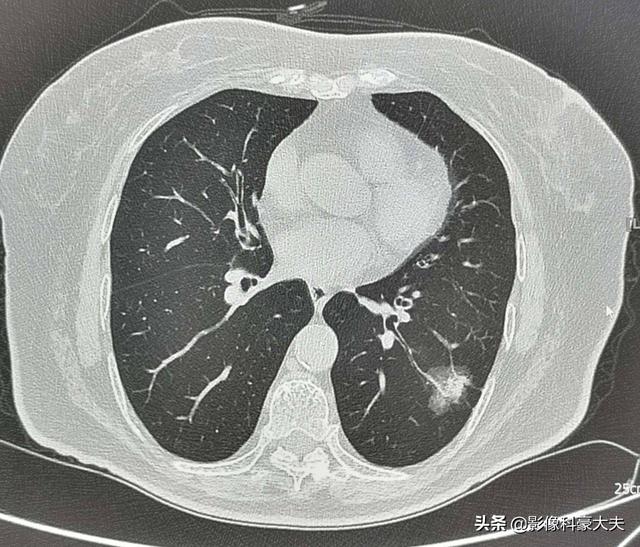

例えば、左下肺に2.2cmの混合膜ガラス結節があるこの中年女性は、リスクの高い結節であり、実際、肺腺癌の典型的な徴候を有している。血管の進入と肥厚を伴う明瞭な地硝子影、気管支気腹徴候、遠位胸膜浸潤、浸潤性肺腺癌の外科的病理所見このような病変は経過観察には勧められないので、転移や治療の遅れを避けるために、さらに詳しく調べてはっきりさせる必要がある。